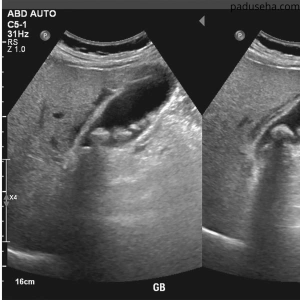

Waspada Dengan Batu Empedu, Atasi Sebelum Makin membesar dan Susah Keluar

Kalau perut kanan kamu sering nyeri, mual datang tiba-tiba, dan makan jadi nggak tenang — itu bukan hal sepele.

Itu tanda batu empedu kamu lagi bermasalah dan kalau terus ditunda, sakitnya bakal makin sering datang.

Ini Yang Bikin Batu Empedu Susah Hilang

Masalahnya bukan cuma di rasa sakit, tapi di dalam tubuh:

Endapan empedu makin mengeras

Lemak nggak keurai sempurna

Aliran empedu tersendat

Tubuh kehilangan keseimbangan

Selama ini nggak dibantu dari dalam, nyeri bakal terus datang.

Kalau Terus Didiemin, Batu Empedu Bisa ‘Mengakar dan Mencakar’

Batu empedu nggak bakal hilang sendiri.

Dan kalau kamu biarin terus, risikonya makin nggak enak:

Nyeri bisa makin hebat sampai bikin kamu nggak bisa berdiri tegak

Bisa muncul demam, mual, muntah

Saluran empedu bisa ikut tersumbat → ini yang bikin kondisi makin kacau